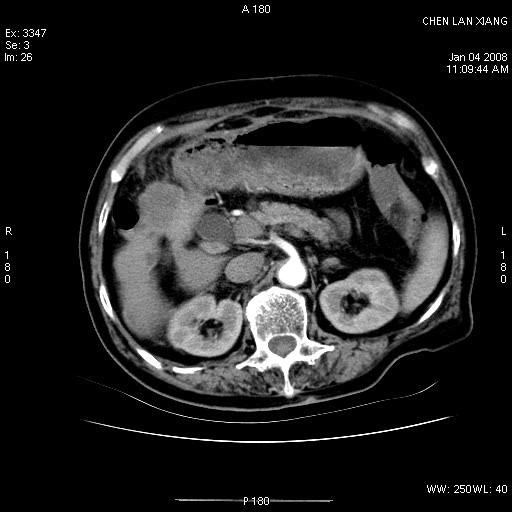

女,76岁,腹痛3-4天,b超示:肝内实性肿物,胆囊强回声,胆总管扩张.

考虑:1、胆总管下端结石伴梗阻性肝内外胆管扩张(肝左叶外侧段肝内胆管多发结石、胆管炎);

2、肿囊癌累及肝,不除外 黄色肉芽肿性胆囊炎。

1 胆总管末端结石伴肝内胆管结石,肝内外胆管扩张。2 胆囊扩大,胆囊壁不规则增厚,内见软组织密度影。考虑:慢性胆囊炎,不除外胆囊癌!

胆囊内结增强影,肝内胆管、胆总管扩张明显。肝内胆管、胆总管下段多发结石,胆囊癌,建议mrcp检查

ct所见:1、 肝内胆管结石,肝内外胆管扩张。低位胆道梗阻,胆总管下端结石;2 胆囊扩大,胆囊壁不规则增厚

考虑:胆总管下端结石并肝内外胆管扩张,肝内胆管结石;